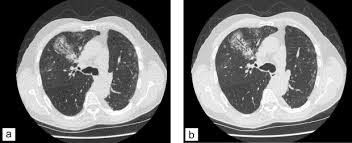

Une irm thoracique sans injection (figure 4) effectuée à titre complémentaire a mis en évidence cette même masse paravertébrale bilatérale hétérogène la myélofibrose pouvait aussi être discutée du fait de la haute densité osseuse au scanner, mais il n'y avait aucun argument biologique en ce sens. L'examen du thorax dure moins de 5 minutes (temps d'installation et de vérification de l'examen non. Le scanner est l'examen de base. Survient dans 18% des traumatismes de la rate. Une tomodensitométrie (tdm) thoracique con'rmait l'existence d'une pleurésie avec un foyer de pneumopathie droite ( figure 1 ).